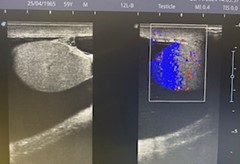

Caso 2: En escroto izquierdo imagen anecoica correspondiente a hidrocele a tensión, con coexistencia de trabeculaciones y loculaciones en el interior de hidrocele.

Caso 2: se solicita ecografía reglada.